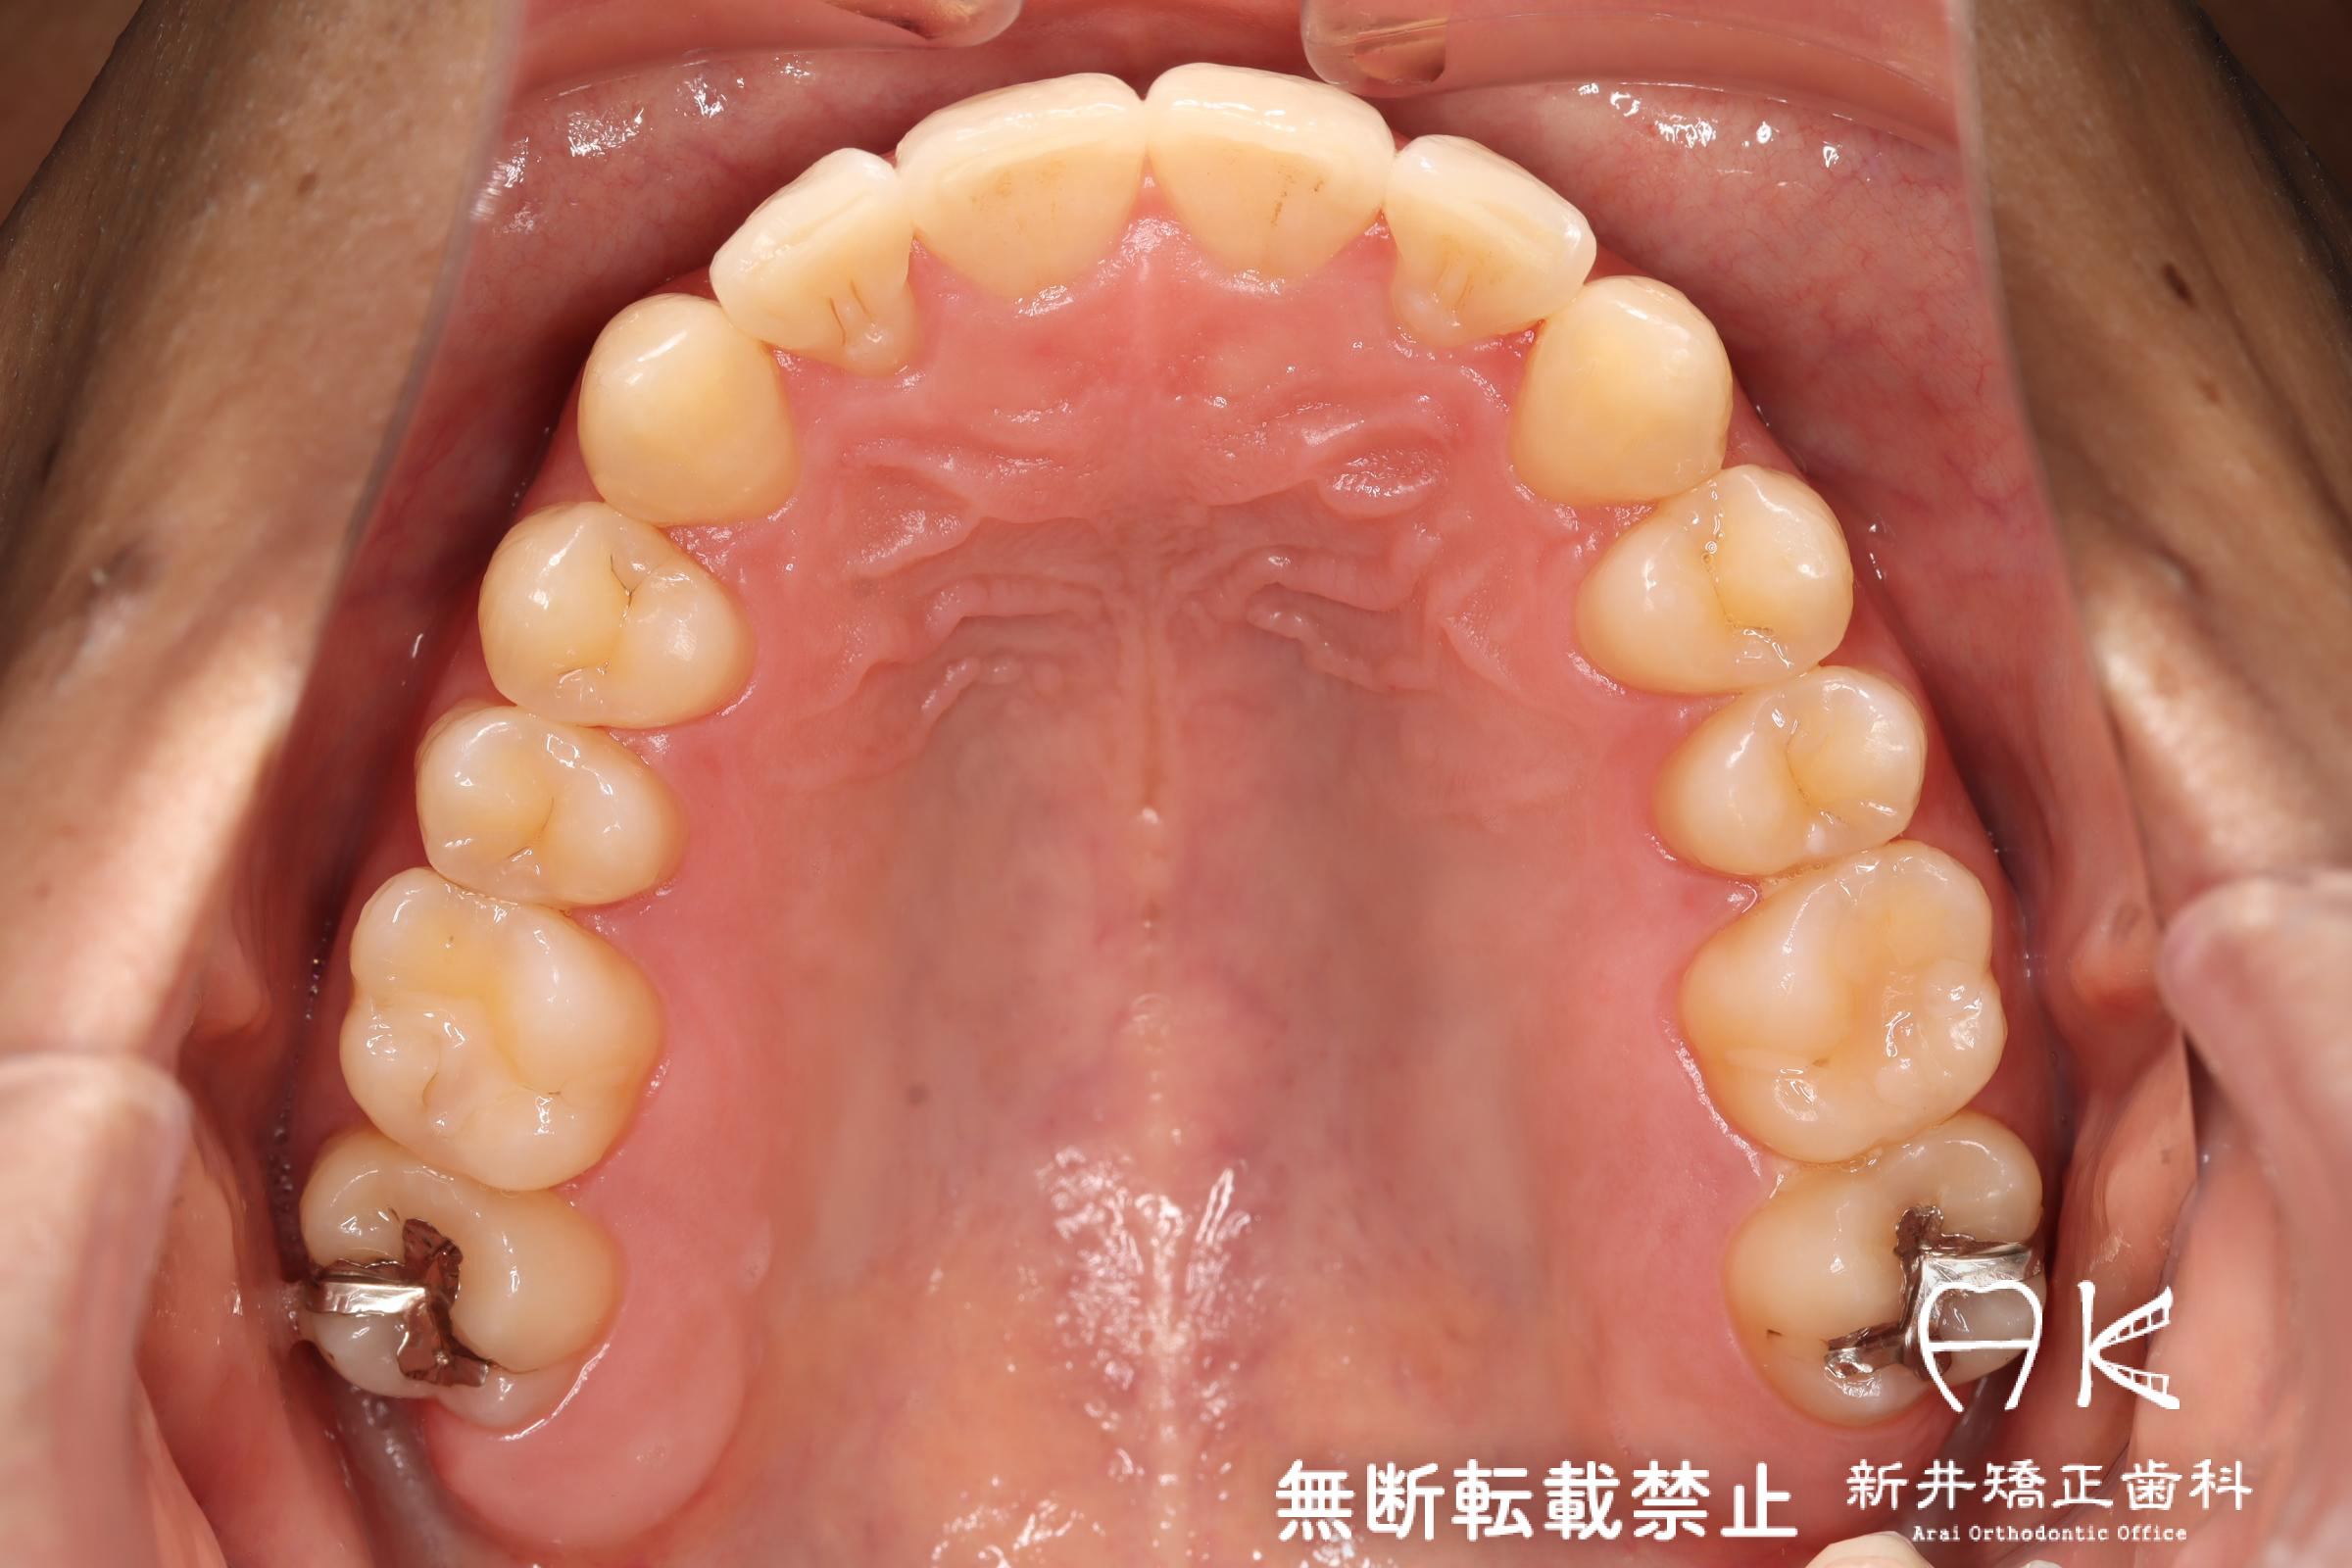

治療前後の解説

| 治療後 | 前歯から奥歯まで全体的に緊密な咬み合わせになっています。 見た目だけでなく、かみ合わせのバランスも良く、歯磨きもしやすい状態となりました。 矯正治療を行うことで、見た目もかみ合わせも良くなり、さらに歯磨きがしやすくなることにより虫歯や歯周病の予防にもなります。 マウスピース型矯正についてはこちらをご覧ください。 https://www.arai-kyousei.jp/invisalign.html |

| 症状・診断名 | 叢生 |

| 抜歯の有無 | 非抜歯 |

| 使用矯正装置 | マウスピース型矯正装置(インビザライン) |